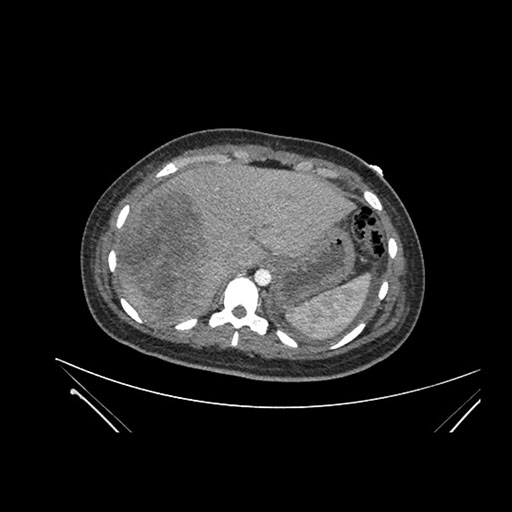

Imaging Analysis

Look through the patient's CT scan to identify any areas of concern for the necessary procedure.

Coronal Arterial

Coronal Venous

Based on initial findings, which issue(s) would you be most concerned about?